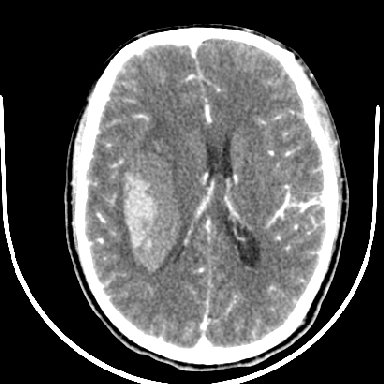

2增强时占位效应加重了,考虑出血还没有停止

但脑出血早期做增强是不是有点太冒险了?

术中抽出40ml陈旧血液,血肿底部似见一条索血管影